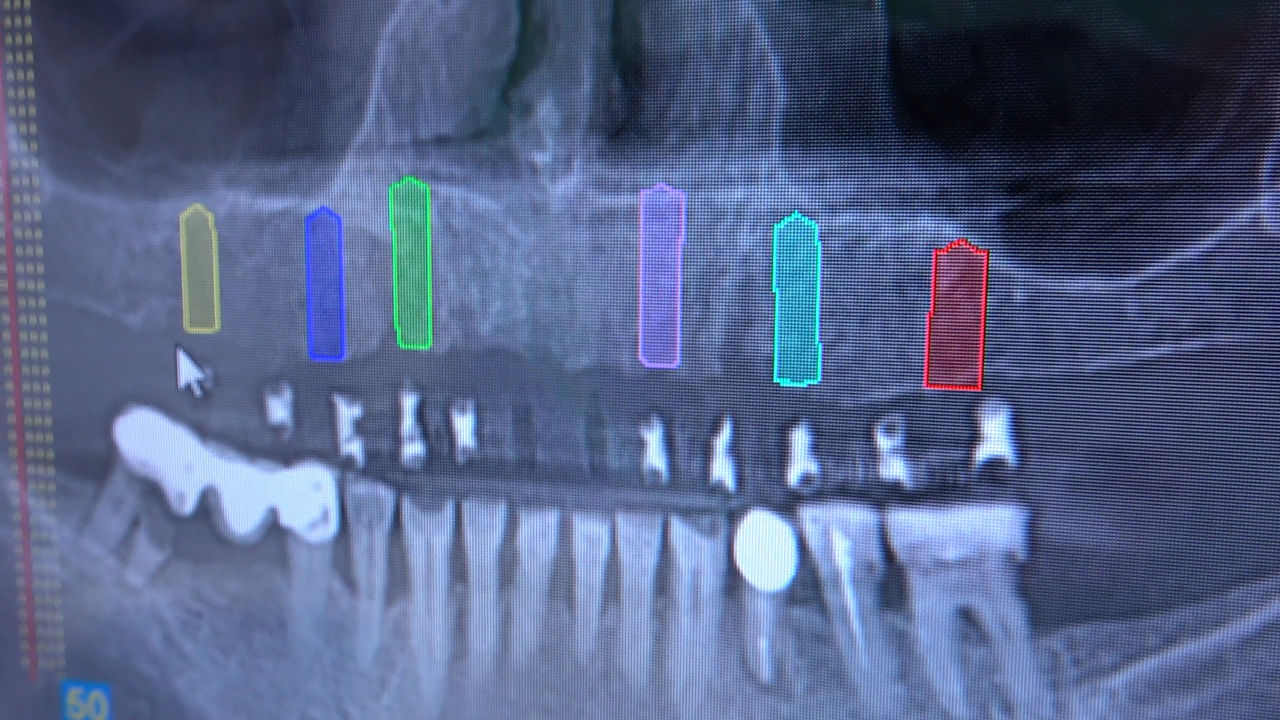

PRACTICULUM IMPLANTOLOGII - SEZON X - SESJA 9 - GRUPA A

Practiculum Implantologii to szkolenie dla adeptów implantologii zorientowane na praktyczne opanowanie procedur zabiegowych i wprowadzenie implantologii do własnej praktyki. Dla Kursantów Grupy A, X Sezonu, 9 Sesja stanowiła ostateczny sprawdzian umiejętności zabiegowych zdobytych podczas procedur wykonywanych w trakcie szkolenia pod kierunkiem dr n.med. Violetty Szycik i dr Małgorzaty Piotrowskiej. Zobacz więcej na: www.practiculum.pl